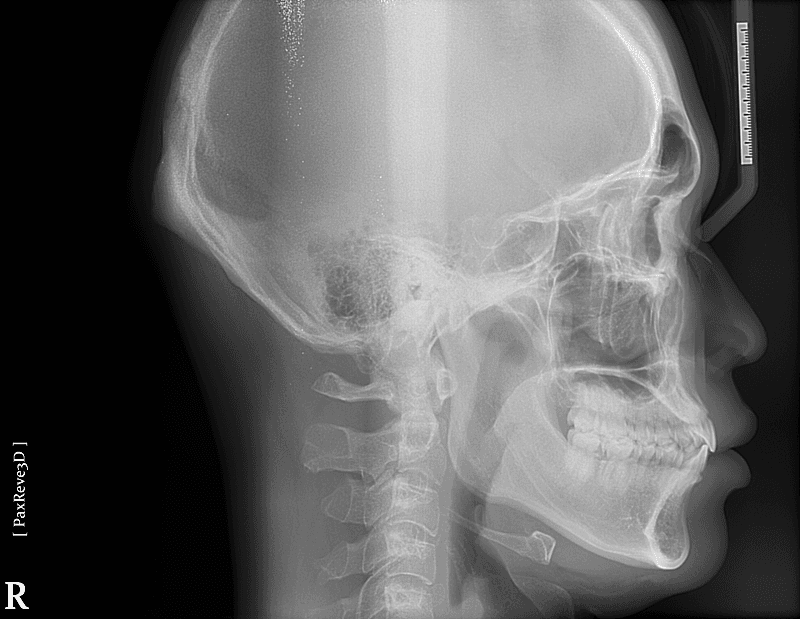

)골격적으로 나온건가요?

2. 해당 정도로는 교정으로 개선이 불가능하며 양악을 하셔야 합니다.